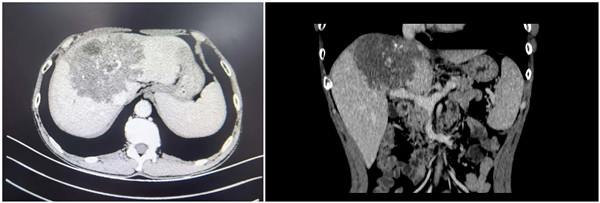

术前CT

术前经过详细缜密的多学科病情讨论和组内商议,陆宏伟教授及团队成员一致认为终末期泡型肝包虫病诊断明确。其中病灶严重侵犯第一、第二、第三肝门,同时侵犯三支静脉的肝腔静脉汇合部,第二肝门水平下腔静脉环周侵犯240度,下腔静脉横向最大侵犯270度,纵向侵袭长度5cm;门静脉左支及右支起始部、右前分支侵犯;病灶侵犯S1、2、3、4、5v、8,若行上述肝段切除,剩余肝体积为546mL,占标准肝体积的47.6%>40%,因此是安全可行的,离体肝切除自体肝移植术是最合适的手术方案。但考虑到患者家庭经济情况,陆宏伟教授决定挑战外科手术禁区,先行在体探查,若无法行病灶与下腔静脉分离,则行下腔静脉人工血管架桥,保留侧第二肝门重建,如若考虑出血风险无法控制或缺血时间超过肝脏耐受极限,则行离体肝切除自体肝移植术。术前充分与家属沟通病情及围术期风险等情况并取得知情同意后,手术如期进行。